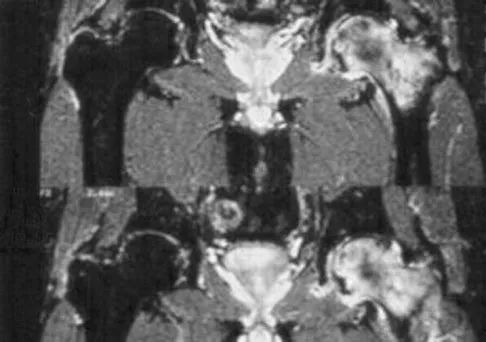

A 38-year-old woman with metastatic thyroid carcinoma has had increasing pain in the left hip for the past 3 months. An AP radiograph and coronal T1-weighted MRI scan are shown in Figures 28a and 28b. Management should consist of

Explanation